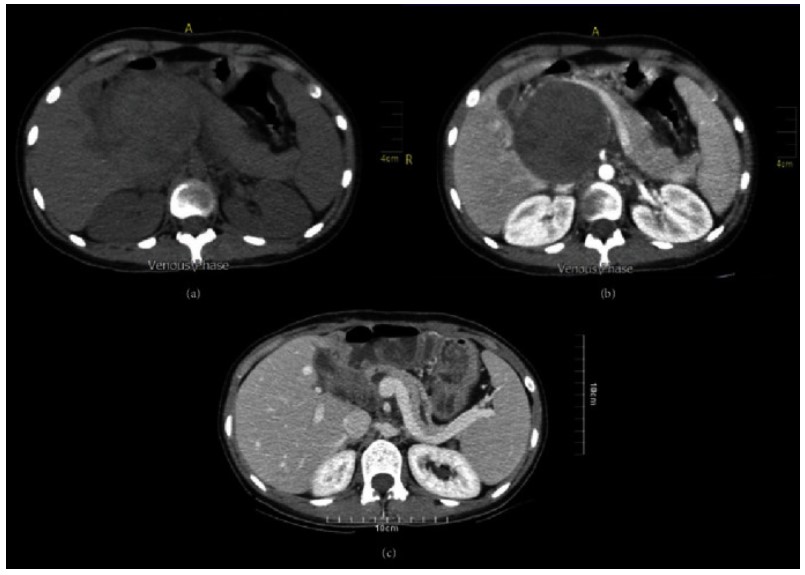

- Small SPNs (< 3cm in diameter) usually appear as completely solid tumors with sharp margins and gradually enhancing, well encapsulated masses in the pancreas and may demonstrate varying amounts of hemorrhage.

- Large lesions have mixed solid – cystic components showing early weak enhancement with gradual increase in enhancement in the hepatic venous phase.